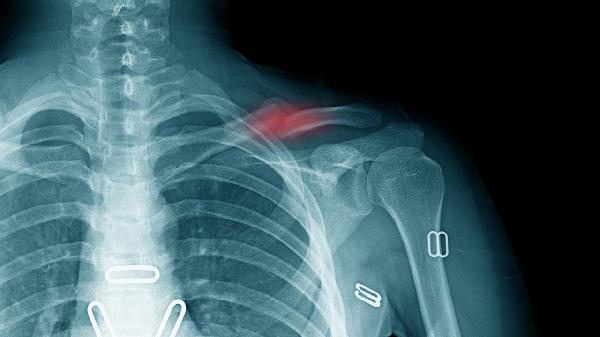

胸痛中心建设过程中需重点解决区域协同问题,建立基层医院与上级医院的转诊机制,推广标准化胸痛评估工具。对于急性冠脉综合征、主动脉夹层、肺栓塞等高危胸痛患者,时间管理直接影响预后,因此建设过程中需强化时钟统一、先救治后收费等制度保障。持续改进环节需建立病例回顾制度,分析时间延误原因并优化流程,同时通过模拟演练提升团队配合效率。